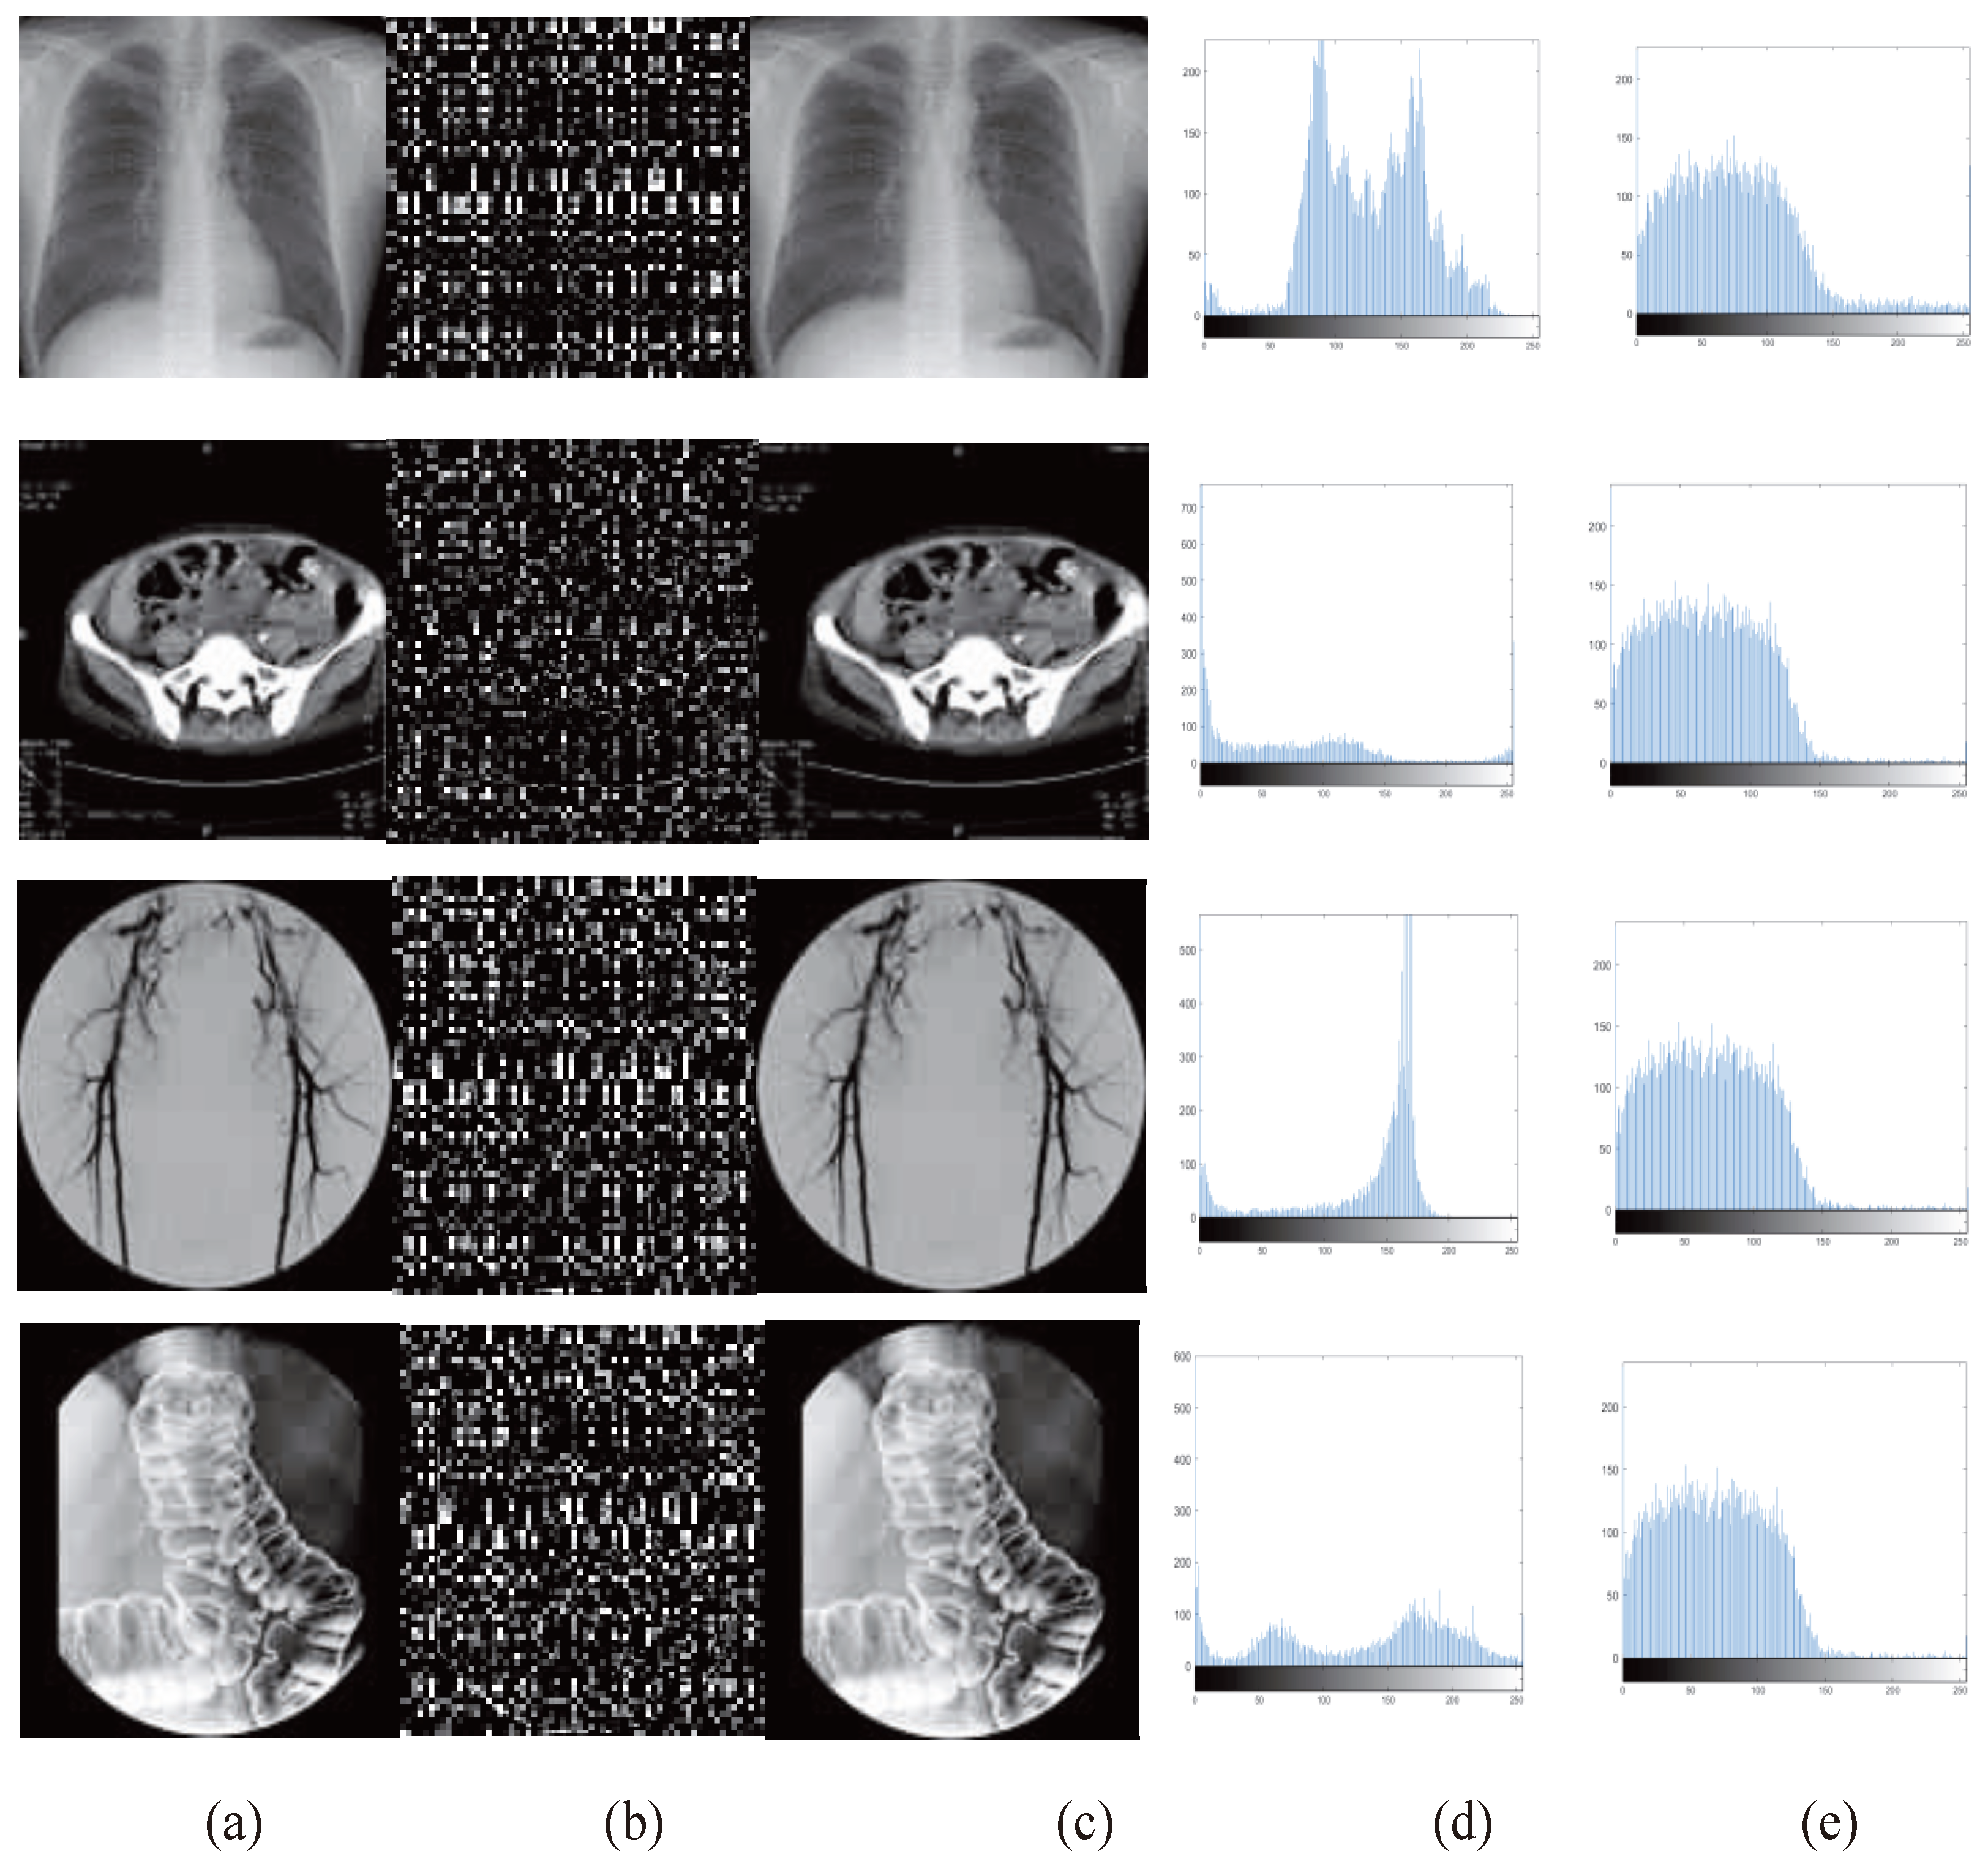

4.1. Perceptual Effect

4.3. Histogram Analysis

| Image No. | (a) | (b) | (c) | (d) | (e) |

|---|---|---|---|---|---|

| 1 | 5.7615 | 7.3832 | 7.4264 | 7.9056 | 5.7615 |

| 2 | 5.7336 | 7.4245 | 7.3967 | 7.6865 | 5.7336 |

| 3 | 6.7269 | 7.2968 | 7.2965 | 7.8589 | 6.7269 |

| 4 | 6.3829 | 7.4510 | 7.2910 | 7.6912 | 6.3829 |

| 5 | 5.8691 | 7.6023 | 7.3703 | 7.8359 | 5.8619 |